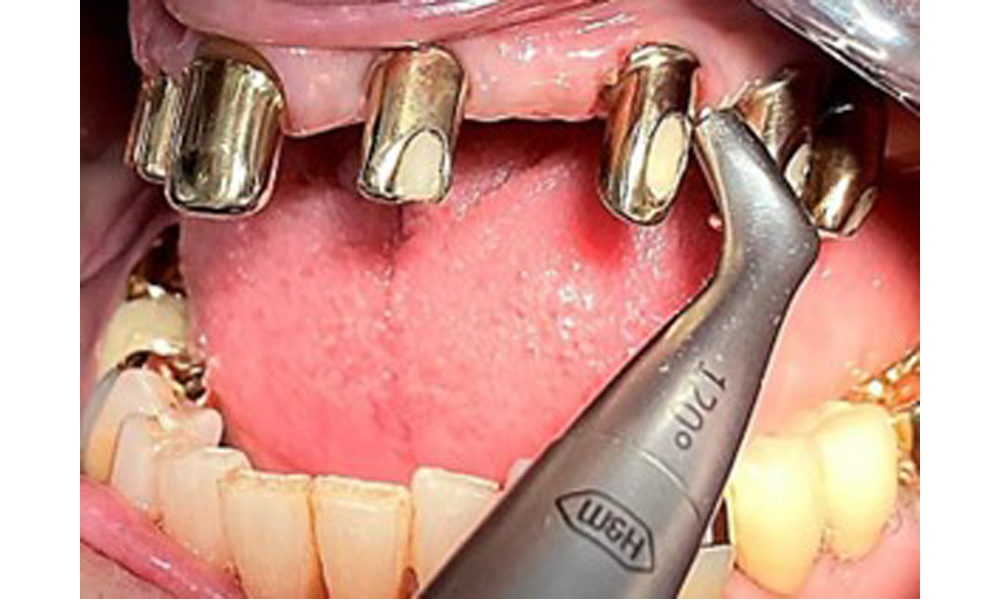

In der Instrumentierung der Therapiesitzung sind bezüglich der Methodenwahl aufgrund des gesunden Allgemeinzustands der Patientin keine Einschränkungen gegeben. Zur Vorbeugung einer Erkrankungsprogression ist die regelmäßige supra- und subgingivale Instrumentierung unerlässlich (7). Die Wahl der Instrumente zur mechanischen Biofilmentfernung ist aus allgemeingesundheitlicher Sicht nicht eingeschränkt und erfolgt bedarfsgerecht. (Sollten stärkere gingivale Entzündungen vorhanden sein, ist bei der Pulverstrahlmethode möglicherweise durch die Einnahme von ASS 100 eine erhöhte Blutungsneigung zu erwarten.)

Bearbeitung der Implantatoberfläche mit Handinstrumenten aus Titan.

Abb. 10: Bearbeitung der Implantatoberfläche mit Handinstrumenten aus Titan.

Darstellung einer Peek-Ultraschallspitze (hier Proxeo Ultra, Firma W&H) zur Bearbeitung von Implantatoberflächen bei mineralisierten Belägen (mineralisierte Beläge sind im vorliegenden Fall nicht vorhanden, schematische Darstellung).

Abb. 11: Darstellung einer Peek-Ultraschallspitze (hier Proxeo Ultra, Firma W&H) zur Bearbeitung von Implantatoberflächen bei mineralisierten Belägen (mineralisierte Beläge sind im vorliegenden Fall nicht vorhanden, schematische Darstellung).

Für die Entfernung von Zahnstein und Konkrementen am natürlichen Zahn kann Schall Ultraschall verwendet werden sowie konventionelle Handinstrumente (8). An den Implantaten sind für mineralisierte Beläge Titan- oder Kunststoffküretten (Abb. 10) einzusetzen oder ein Kunststoff- bzw. Peek-Ansatz (Abb. 11) für die Ultraschallbehandlung, um die Implantatoberfläche nicht zu beschädigen.